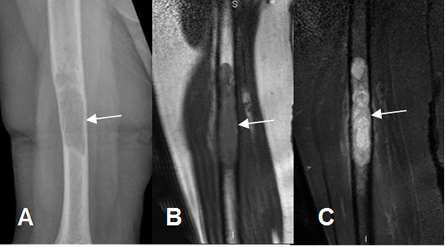

Fig 13 A. Reemplazo de medula ósea.

A: Rx AP. Lesión osteolítica en el tercio medio del fémur.

B: RM sagital en T1 y B: RM sagital en STIR. Lesión hipointensa en T1 e hiperintensa en STIR, que reemplaza la MO normal, por metástasis de tumor renal.